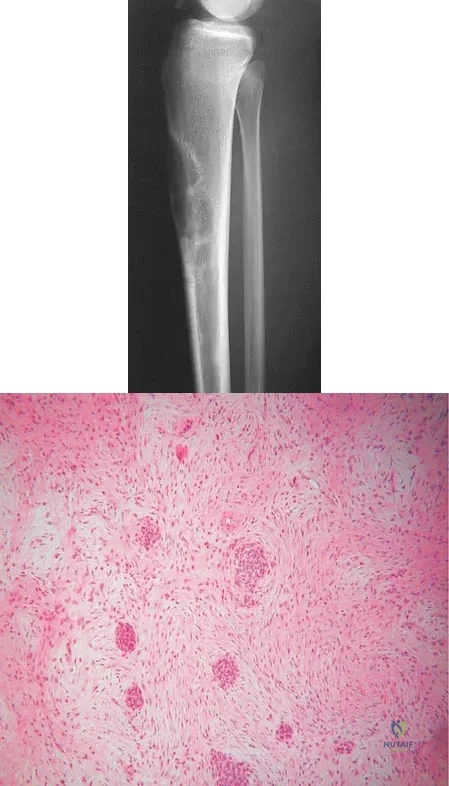

A 16-year-old girl has had anterior leg pain and a mass for the past 8 months. Figures 2a and 2b show a radiograph and an H & E histologic specimen. Which of the following disorders is believed to be a precursor of this lesion?

Explanation